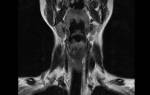

В первую очередь, необходимо отметить, что такое обструкция дыхательных путей. Так называют синдром непроходимости дыхательного тракта человека. Такой процесс может наблюдаться в любом отделе верхних дыхательных путей.

Несмотря на точную причину обструкции дыхательных путей у детей и взрослых, данное заболевание представляет собой довольно опасное осложнение, которое отличается нарастающей гипоксией. Наиболее часто встречаемой причиной асфиксии, в случае отравления успокоительными средствами или обморочным состоянием, называют западение языка.

Не менее распространенной причиной возможной непроходимости является спазм и отекание ых связок. Обструкцию такого типа могут вызывать кровотечения и ожоги, в то время как у детей данное состояние может появляться после инфекционных заболеваний.